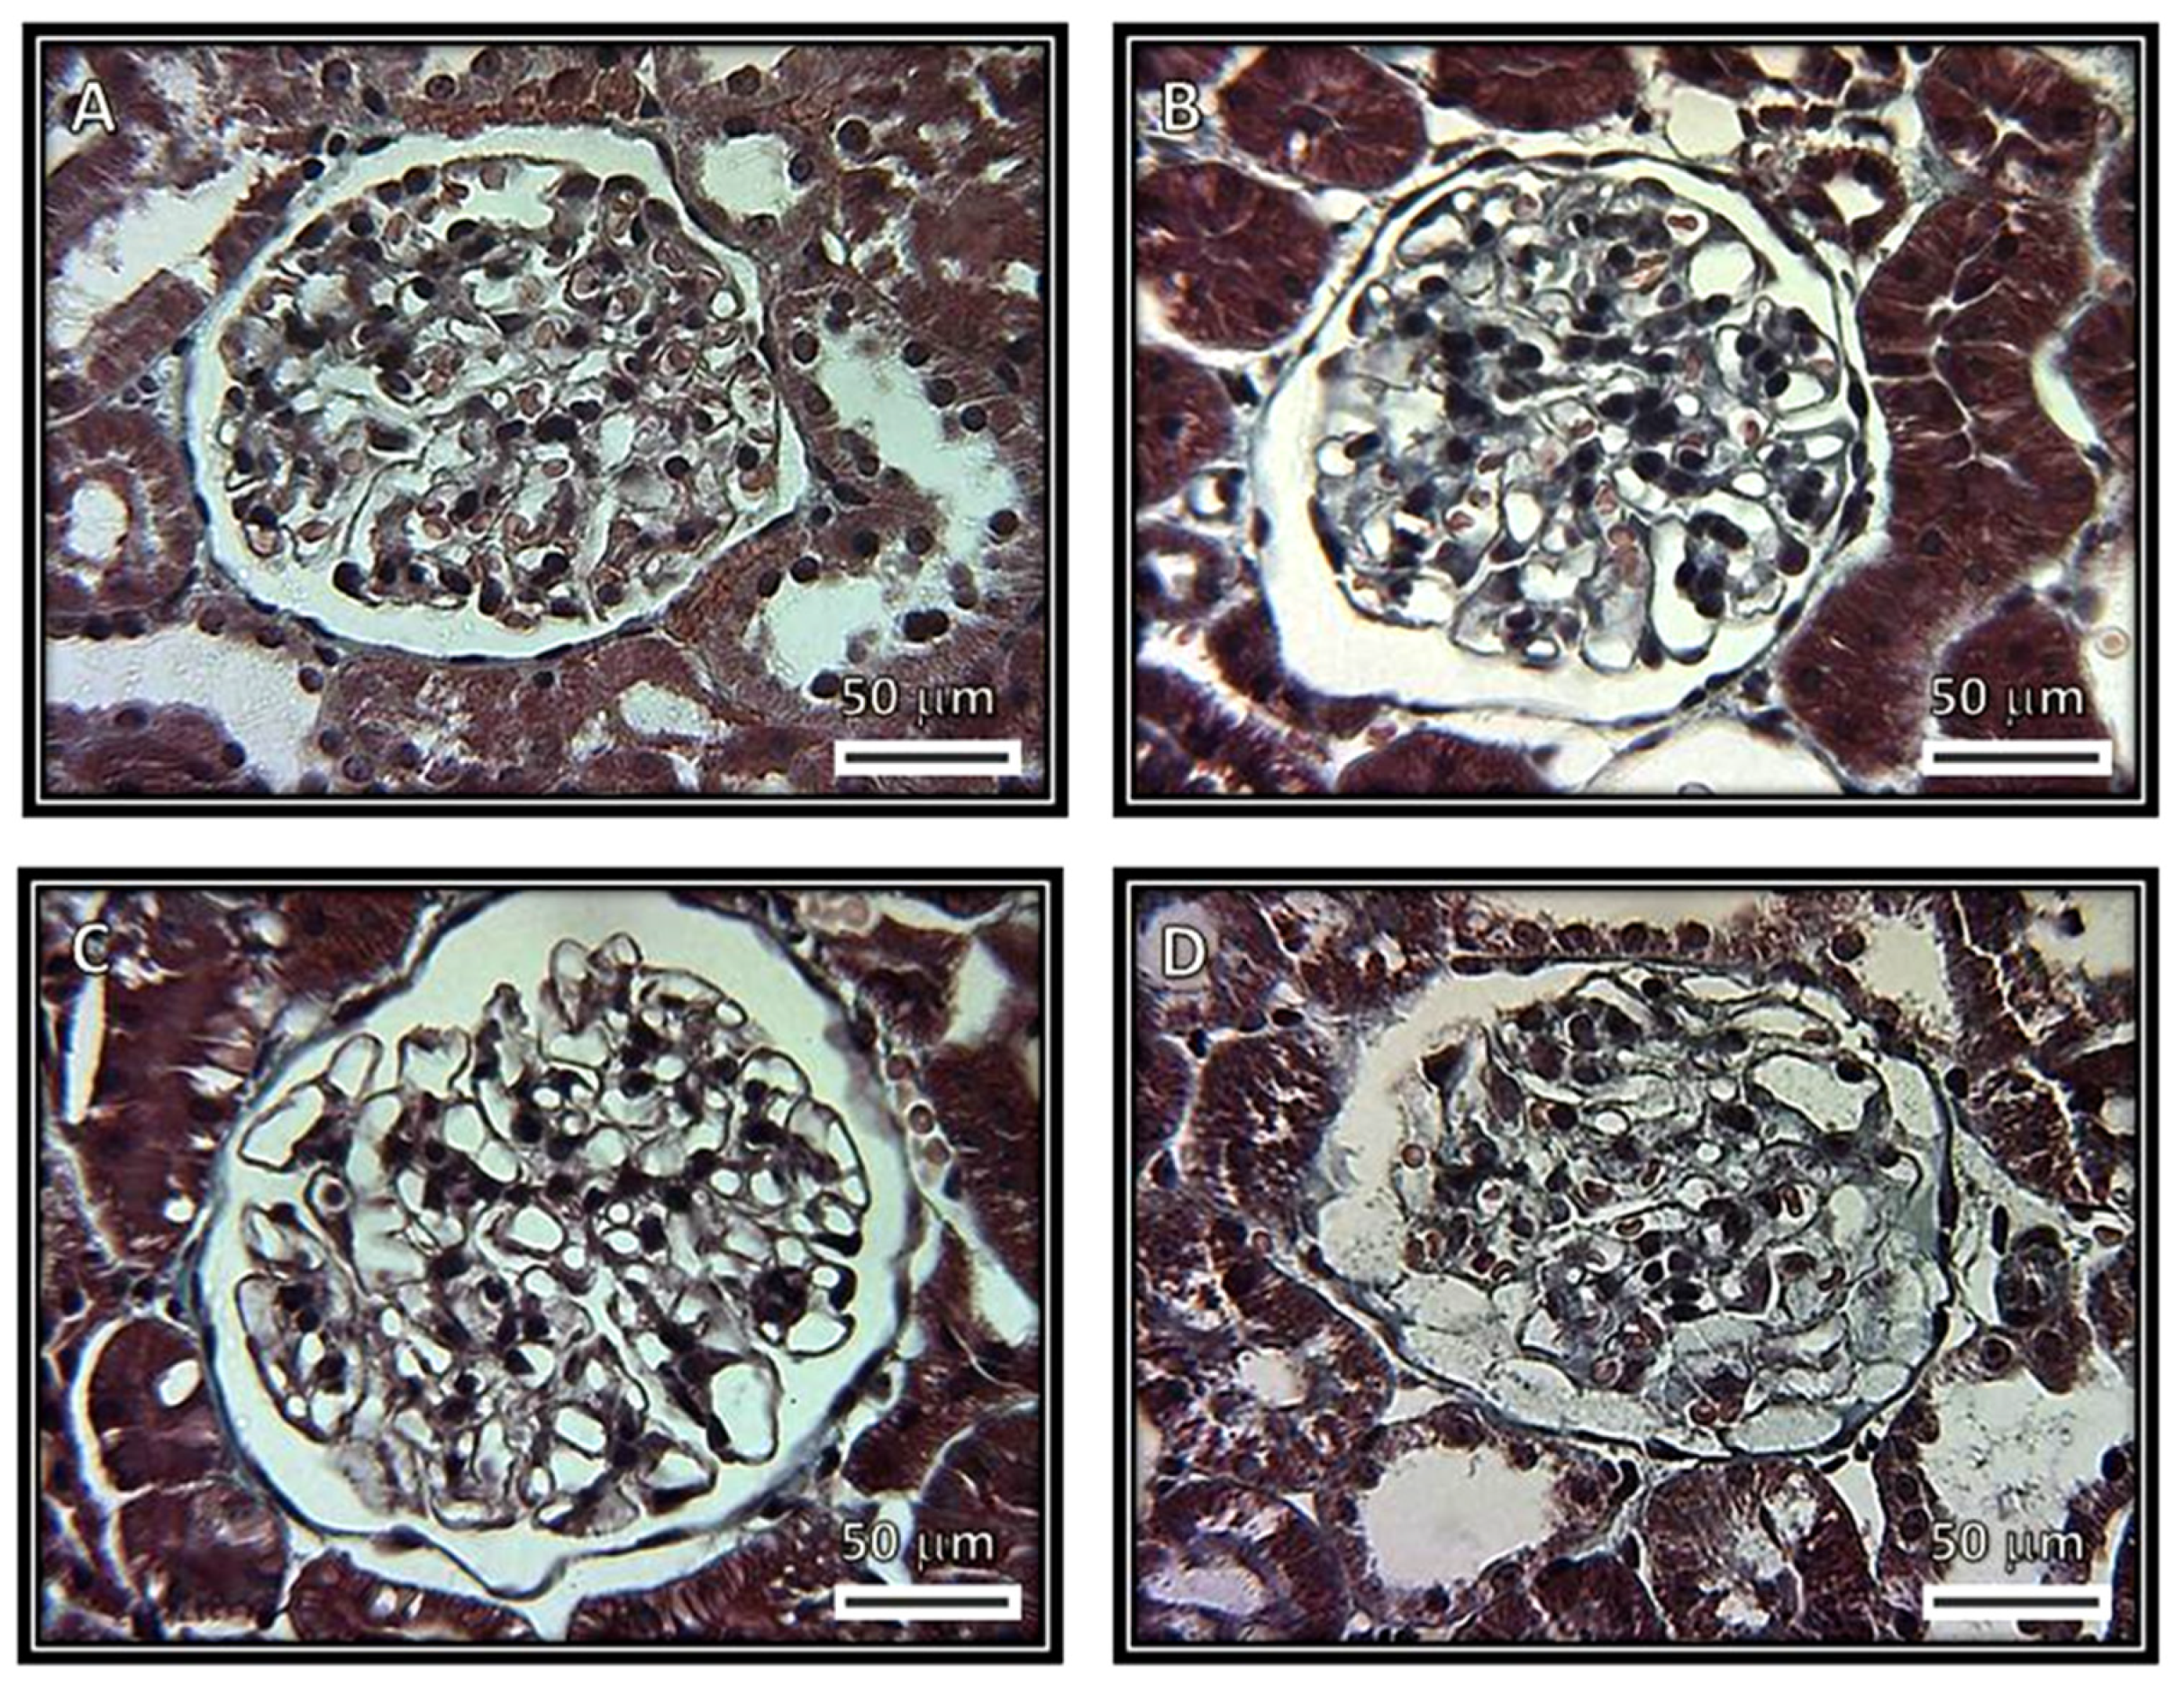

Figure 1, Figure 2, Figure 3 and Figure 4 show representative photomicrographs of the renal cortexes from the kidneys of the experimental groups. The glomeruli showed open capillary loops, basement membranes and Bowman’s capsules positive for PAS staining in the C, SS and HS groups. (Figure 1, Panels A–C), and Masson and Jones’ methenamine staining in the C, SS and HS groups (Figure 3, Panels A–C, and Figure 4, Panels A–C, respectively). However, in the rats injected with the serum from CG patients, the glomeruli showed podocyte hypertrophy, a reduced glomerular size, retraction of the tuft and prominent visceral cells. There was an increase in the urinary space, with some vacuoles in it and with and without immunolabeling for TNFα and WT1 (Figure 5 and Figure 6), respectively. These changes are possibly a precursory finding for glomerular collapse; however, glomerular loop collapse was not clearly demonstrated. Probably, a longer time of evolution would be needed to observe glomerular collapse (Panel D).

The glomeruli from rats that received serum from patients with CG show a diffuse glomerular tuft retraction. The tubules do not show alterations in the first three groups, but in the CG group, the PAS staining is positive in the proximal convoluted tubules, and there are vacuoles and edema (Figure 2).

Figure 1. Representative photomicrographs of rat renal cortexes. The images show glomeruli from (A) control, (B) kidneys from rats injected with saline solution and (C) kidneys from rats injected with serum from healthy subjects. Open capillary loops, basement membranes and Bowman’s capsules positive for periodic acid–Schiff stain (PAS) staining can be observed in these panels. (D) Kidneys from rats that were injected with serum from patients with collapsing glomerulopathy. Retraction of the glomerular tuft, podocyte hypertrophy and injury, increased urinary space and presence of some vacuoles in the urinary space can be observed. (Periodic acid–Schiff stains, 400×.)